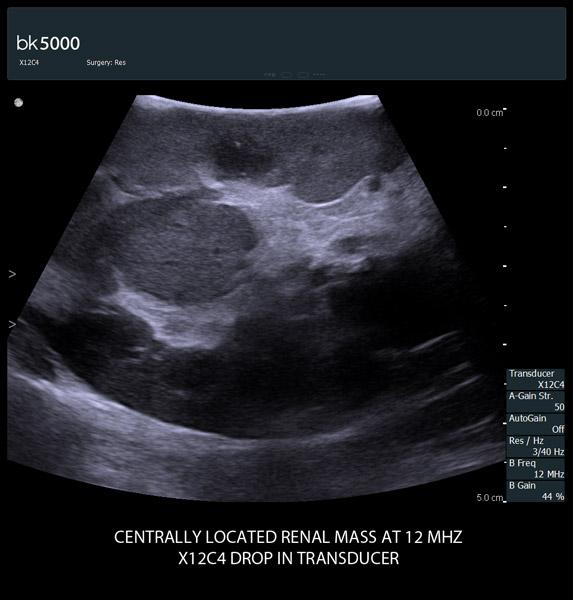

The unique Drop-In transducer enables access and visualization of complex organs and difficult-to-access anatomy in real-time. For example, in kidney navigation and difficult-to-access endophytic and exophytic tumors, the small, compact, curved linear array Drop-In transducer enables a wider field of view for faster examinations. The specially-designed fin grasped by the robotic arm ensures maximum control and organ contact so you can get the information you need.